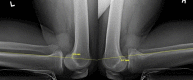

The posterior cruciate ligament (PCL) is known to be the main posterior stabilizer of the knee. Anatomic single-bundle PCL reconstruction, focusing on reconstruction of the larger anterolateral bundle, is the most commonly performed procedure. Because of the residual posterior and rotational tibial instability after the single-bundle procedure and the inability to restore the normal knee kinematics, an anatomic double-bundle PCL reconstruction has been proposed in an effort to re-create the native PCL footprint more closely and to restore normal knee kinematics. We detail our technique for an anatomic double-bundle PCL reconstruction using Achilles and anterior tibialis tendon allografts.